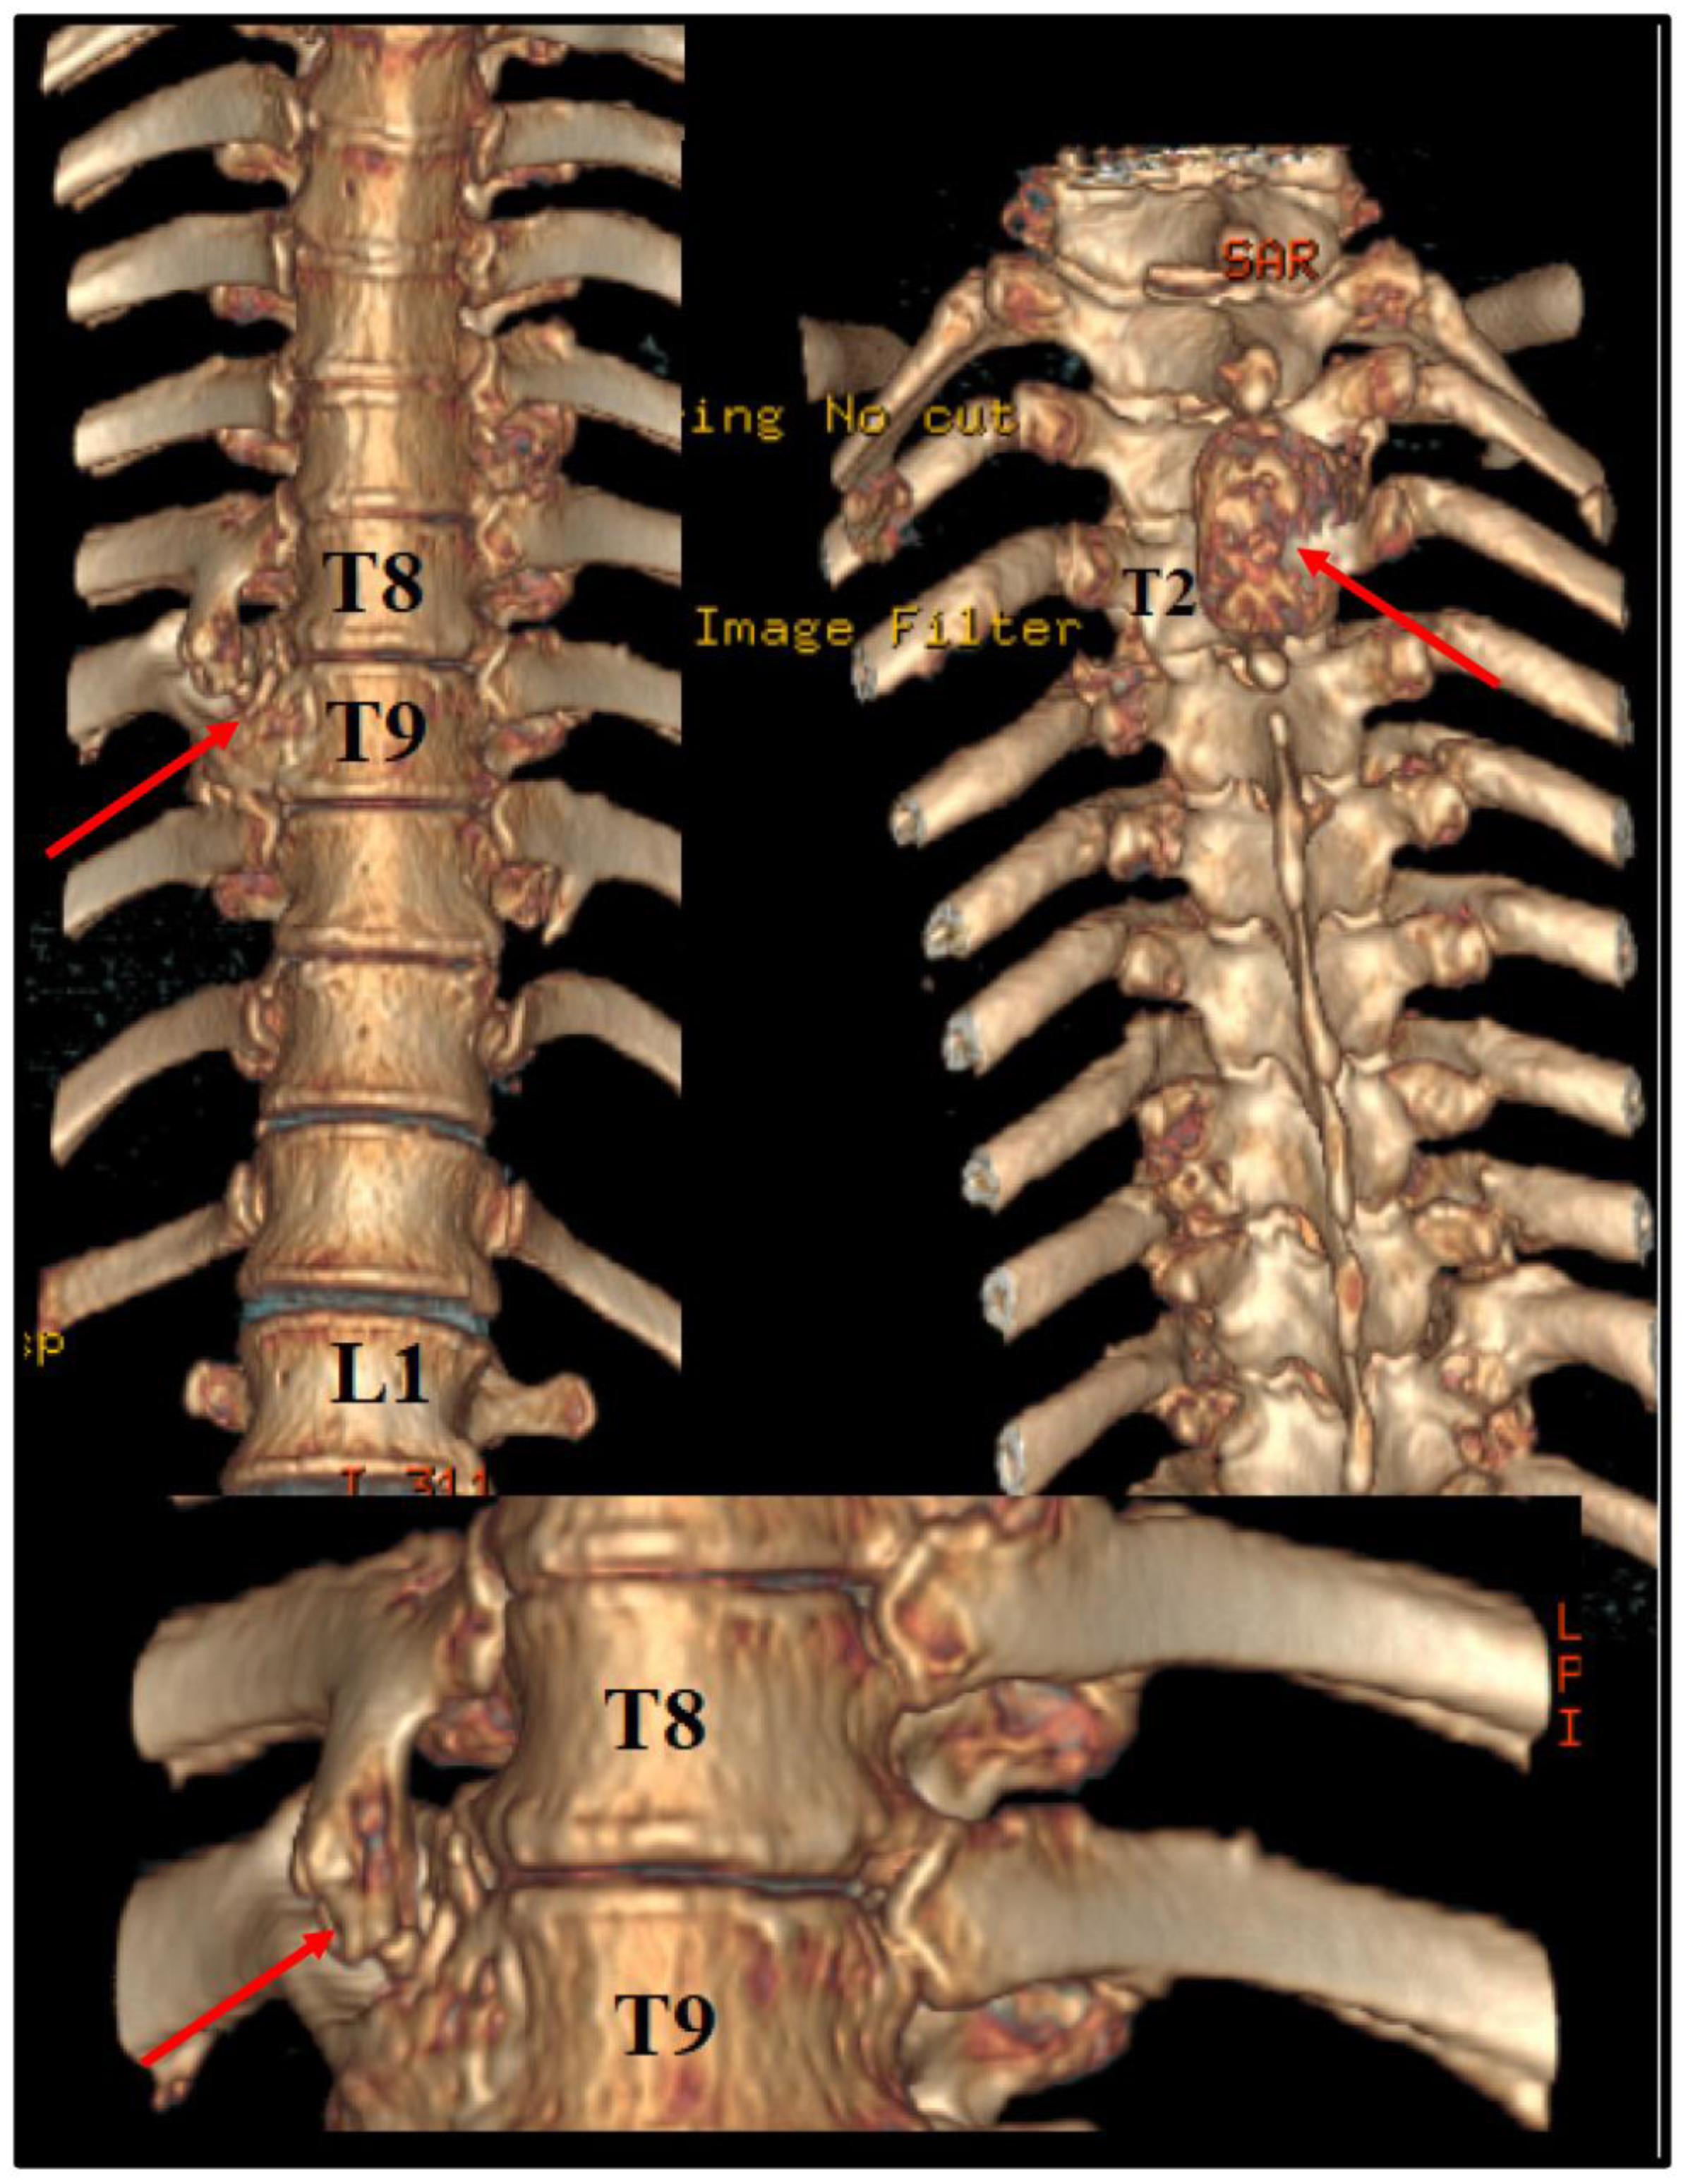

Before the intervention, we asked for a 3D CT reconstruction, which helped to appreciate the exterior aspect of the vertebral column, as well as to acknowledge the outer extensions of the exostosis (Figure 2).

Figure 2. Preoperative 3D CT scan. Note the outer margins of the osteochondroma, along with another one, localized at T2 level, which was neurologically silent.

As shown in Figure 1, the osteochondroma occupied roughly three-quarters of the whole caliber of the medullary canal. Using the CT scan, the mass showed a bony signal with a homogenous composition. The shift of the spinal cord was very relevant, as the patient could not walk, or maintain orthostatism or sphincter control.